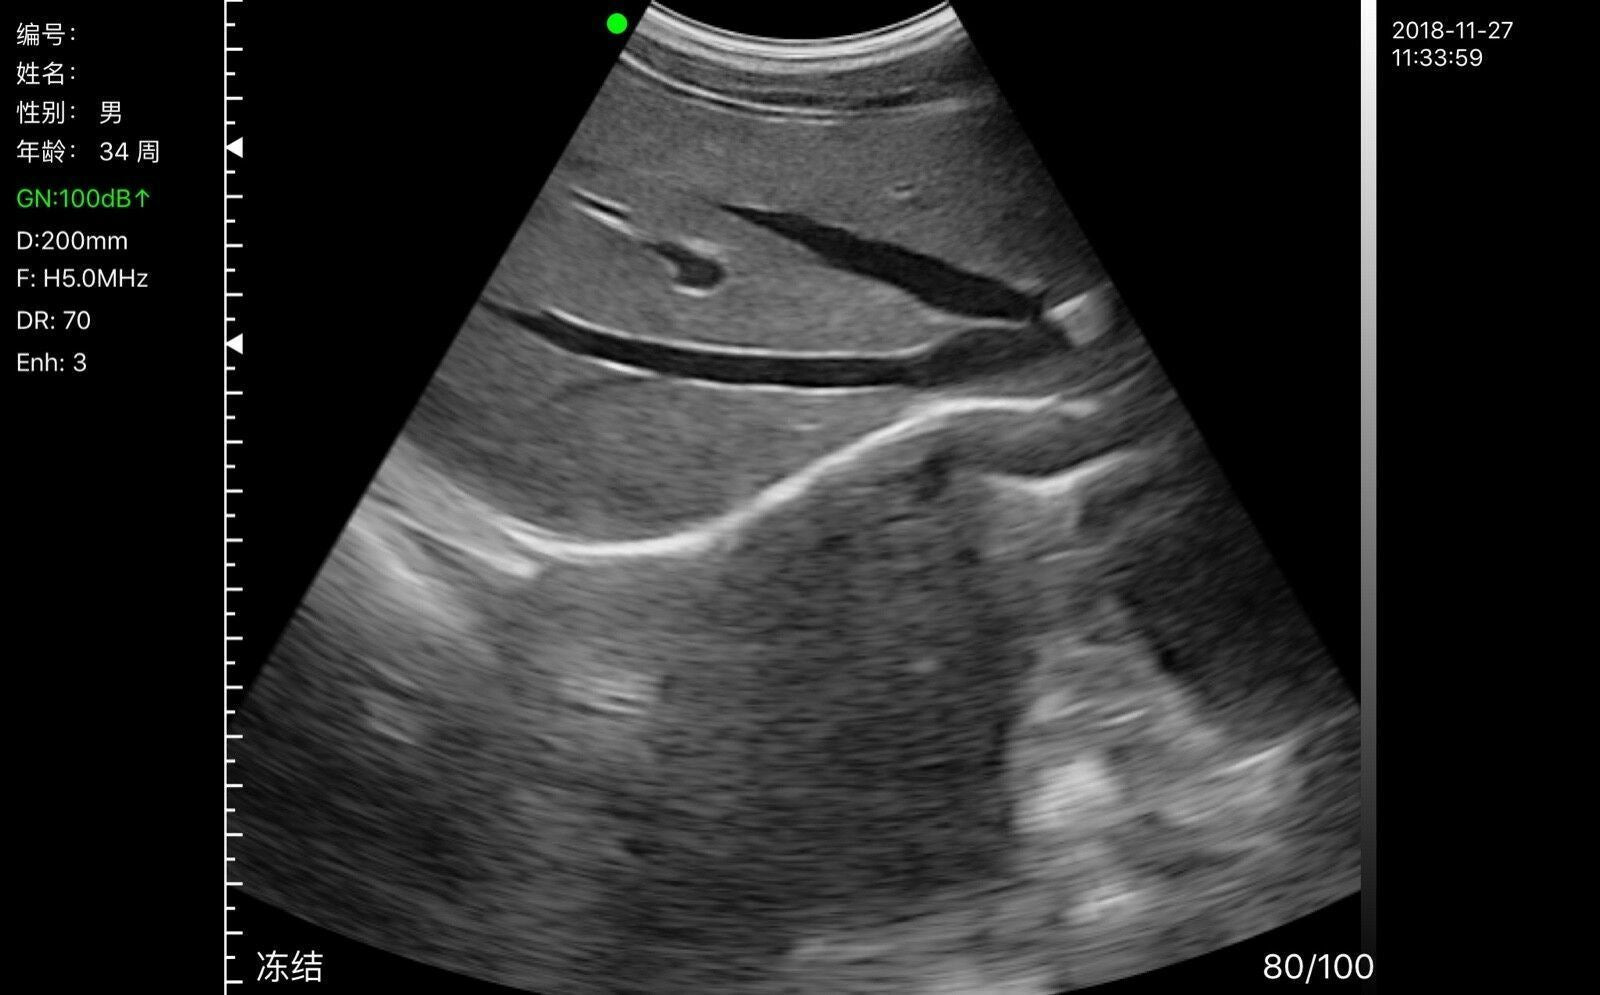

- Display Mode: B, B/M, Color, PW, PDI

- DR: 40-100

- Image grayscale: 256 level

- Field of View: 80 degree

- Gain: 30-205Db

- Measurement: Length, Area, Circumference, GA(CRL, BPD, GS, FL, HC, AC)K